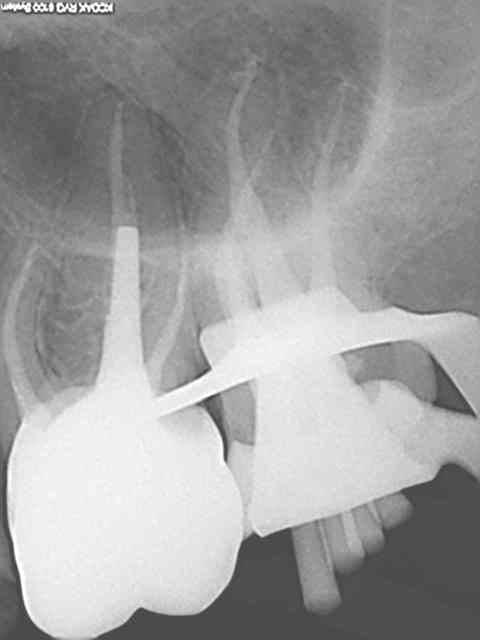

ci joint la radio d'une endo prémolaire hier en 8 minutes chrono

je vous laisse juger la qualité de l'obturation au thermafill

système à vivement conseiller